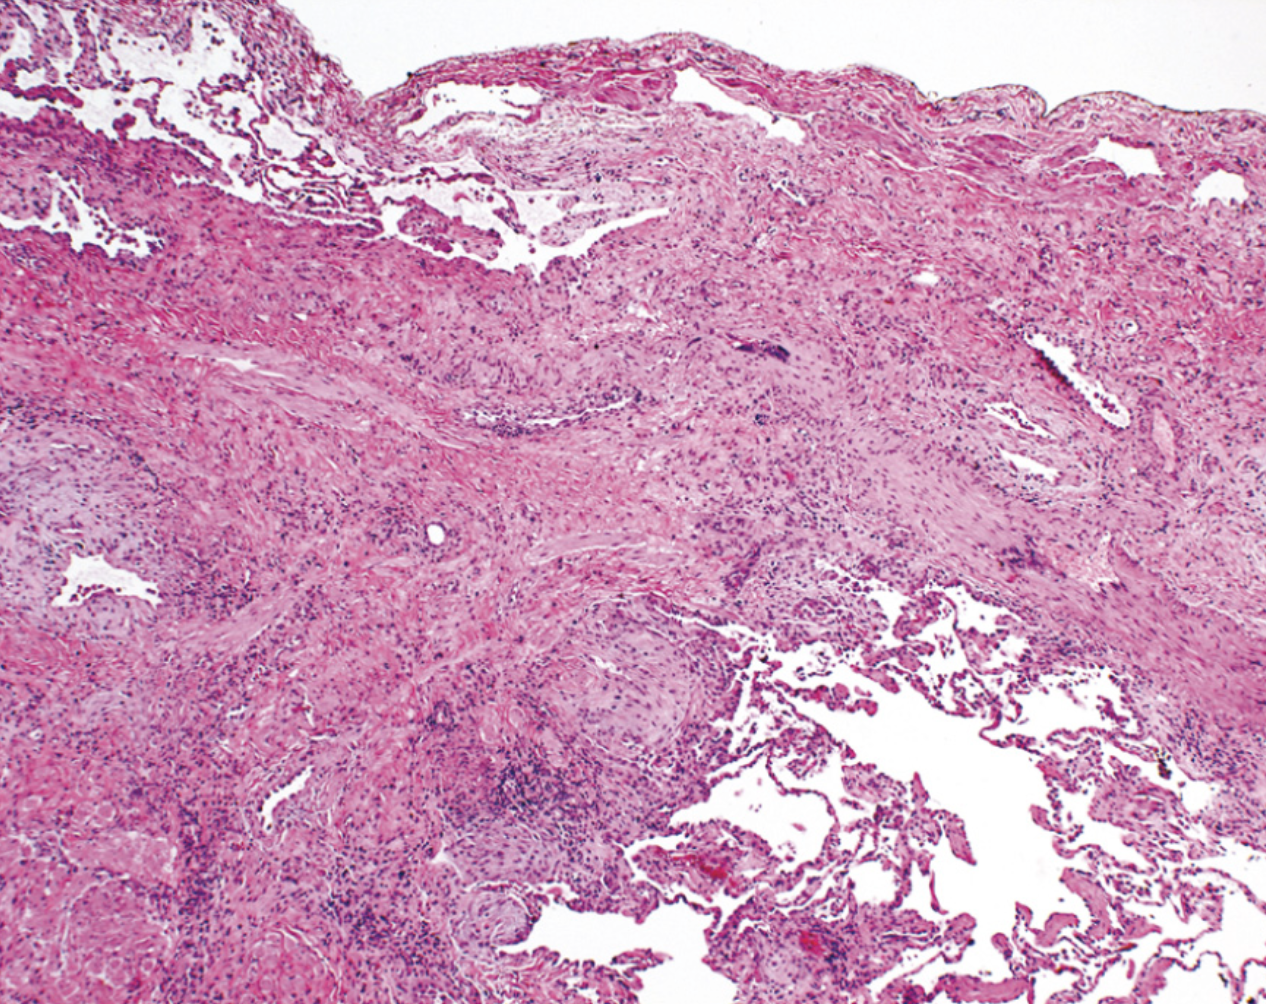

¿Qué es?

Bronquiectasias

Destrucción del músculo liso y tejido elástico deriva a infecciones persistentes y conduce a una dilatación permanente de los bronquios y bronquiolos

¿Cómo se ve morfológicamente las bronquiectasias?

Vias aéreas dilatadas de aspecto quístico llenos de secreción purulenta, afectación bilateral

Bronquiectasia Activa microscópicamente

Esfacelación del epitelio y zonas ulceradas con necrosis

Formación de abcesos

Pseudoestratificación o metaplasia del epitelio residual

Bronquiectasias crónica

Fibrosis de la pared bronquial, que lleva a obliteración de los lúmenes